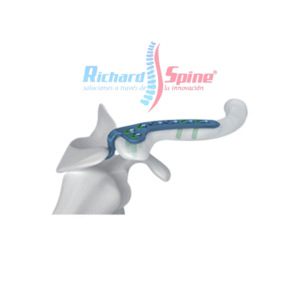

- Columna Vertebral

Malla de Titanio para Columna Cervical

- La malla de titanio está disponible en diferentes alturas para cada patología y condiciones anatómicas. arquitectura abierta para malla de titanio permite la fusión ósea y optimiza el crecimiento óseo y sus anillos extremos paralelos para restaurar la alineación espinal normal y resistir el hundimiento. mientras tanto, se utiliza malla de titanio para Trauma, tumor, espondilolistesis, disco degenerativo enfermedad.